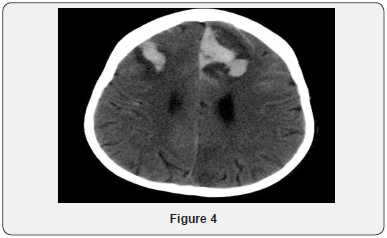

Echocardiogram Holter monitor and Eye examination all were normal. The patient underwent muscle biopsy which showed mild lipid myopathy with type 2 muscle fiber atrophy, but with no morphological evidence of mitochondrial disease. A stat CT brain showed hemorrhagic infarction and some fresh bleeding in subarachnoid space (not older than 3 days), possibly on the basis of ischemic lesions, considering the further hypodense lesions in the parasagittal area on bi-occipital and parieto-occipital regions, more extended on the left side (Figure 4). The neurosurgery team was notified, but it was determined that the patient has poor prognosis and is not candidate for surgery. Gradually, the patient developed respiratory distress and was transferred to the intensive care unit and required mechanical ventilation. He was monitored continuously by EEG. At that time, he showed subclinical seizures originating from the posterior head region, right side more than left. A burst suppression pattern was established, but during the burst period he was having multifocal spikes and polyspikes. Brain MRI showed massive hemorrhagic infarction of non-vascular distribution pattern involving the posterior occipito-parietal, region with brain stem area and cerebellum (Figures 5-9) and a lesion extending to the temporo-parietal region (Figures 5,7). Cerebral angiography showed multiple territorial hemorrhagic infarctions, with no blood entering intracranially in a case of massive intracranial edema, suggesting brain death (Figure 10). Using homozygosity mapping followed by whole exome sequencing, we identified a homozygous mutation of APOA1BP that caused lethal infantile leukoencephalopathy. The patient continued to deteriorate, then died at the age of four years.